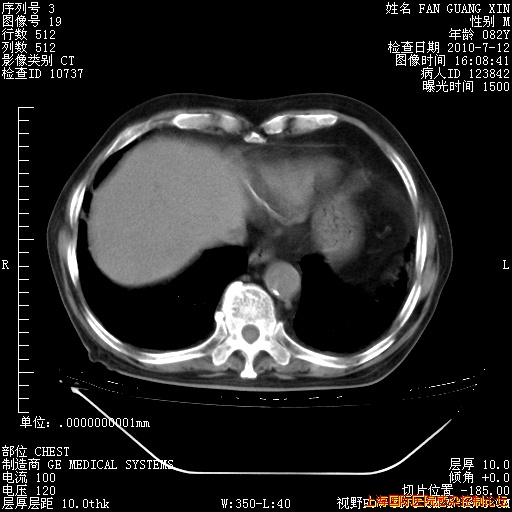

补发6月12日肺部CT肺窗

6月12日肺窗